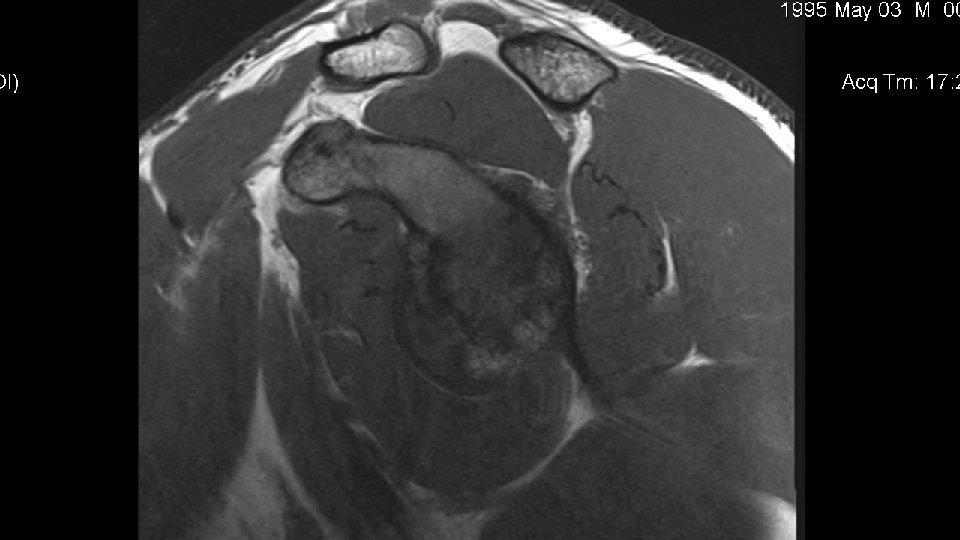

Disposition • The patient was scheduled for MRI